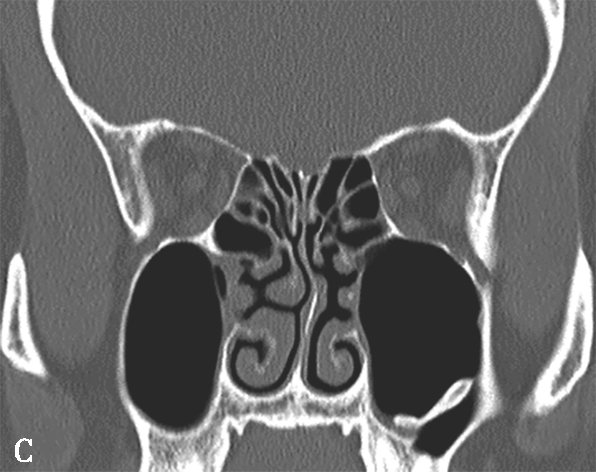

窦口鼻道复合体(ostiomeatal complex,OMC):由于纤维内镜生理性手术的需要,近一二十年来提出了窦口鼻道复合体的概念。窦口鼻道复合体并非一个独立的解剖结构,而是指前组鼻窦自然开口周围的区域,包括中鼻甲、钩突、半月裂、筛漏斗、鼻丘、筛泡、上颌窦自然开口等解剖结构(图1-3-2)。

图1-3-2 窦口鼻道复合体解剖

1.半月裂;2.钩突;3.中鼻道;4.筛大泡;5.筛漏斗;6.上颌窦开口